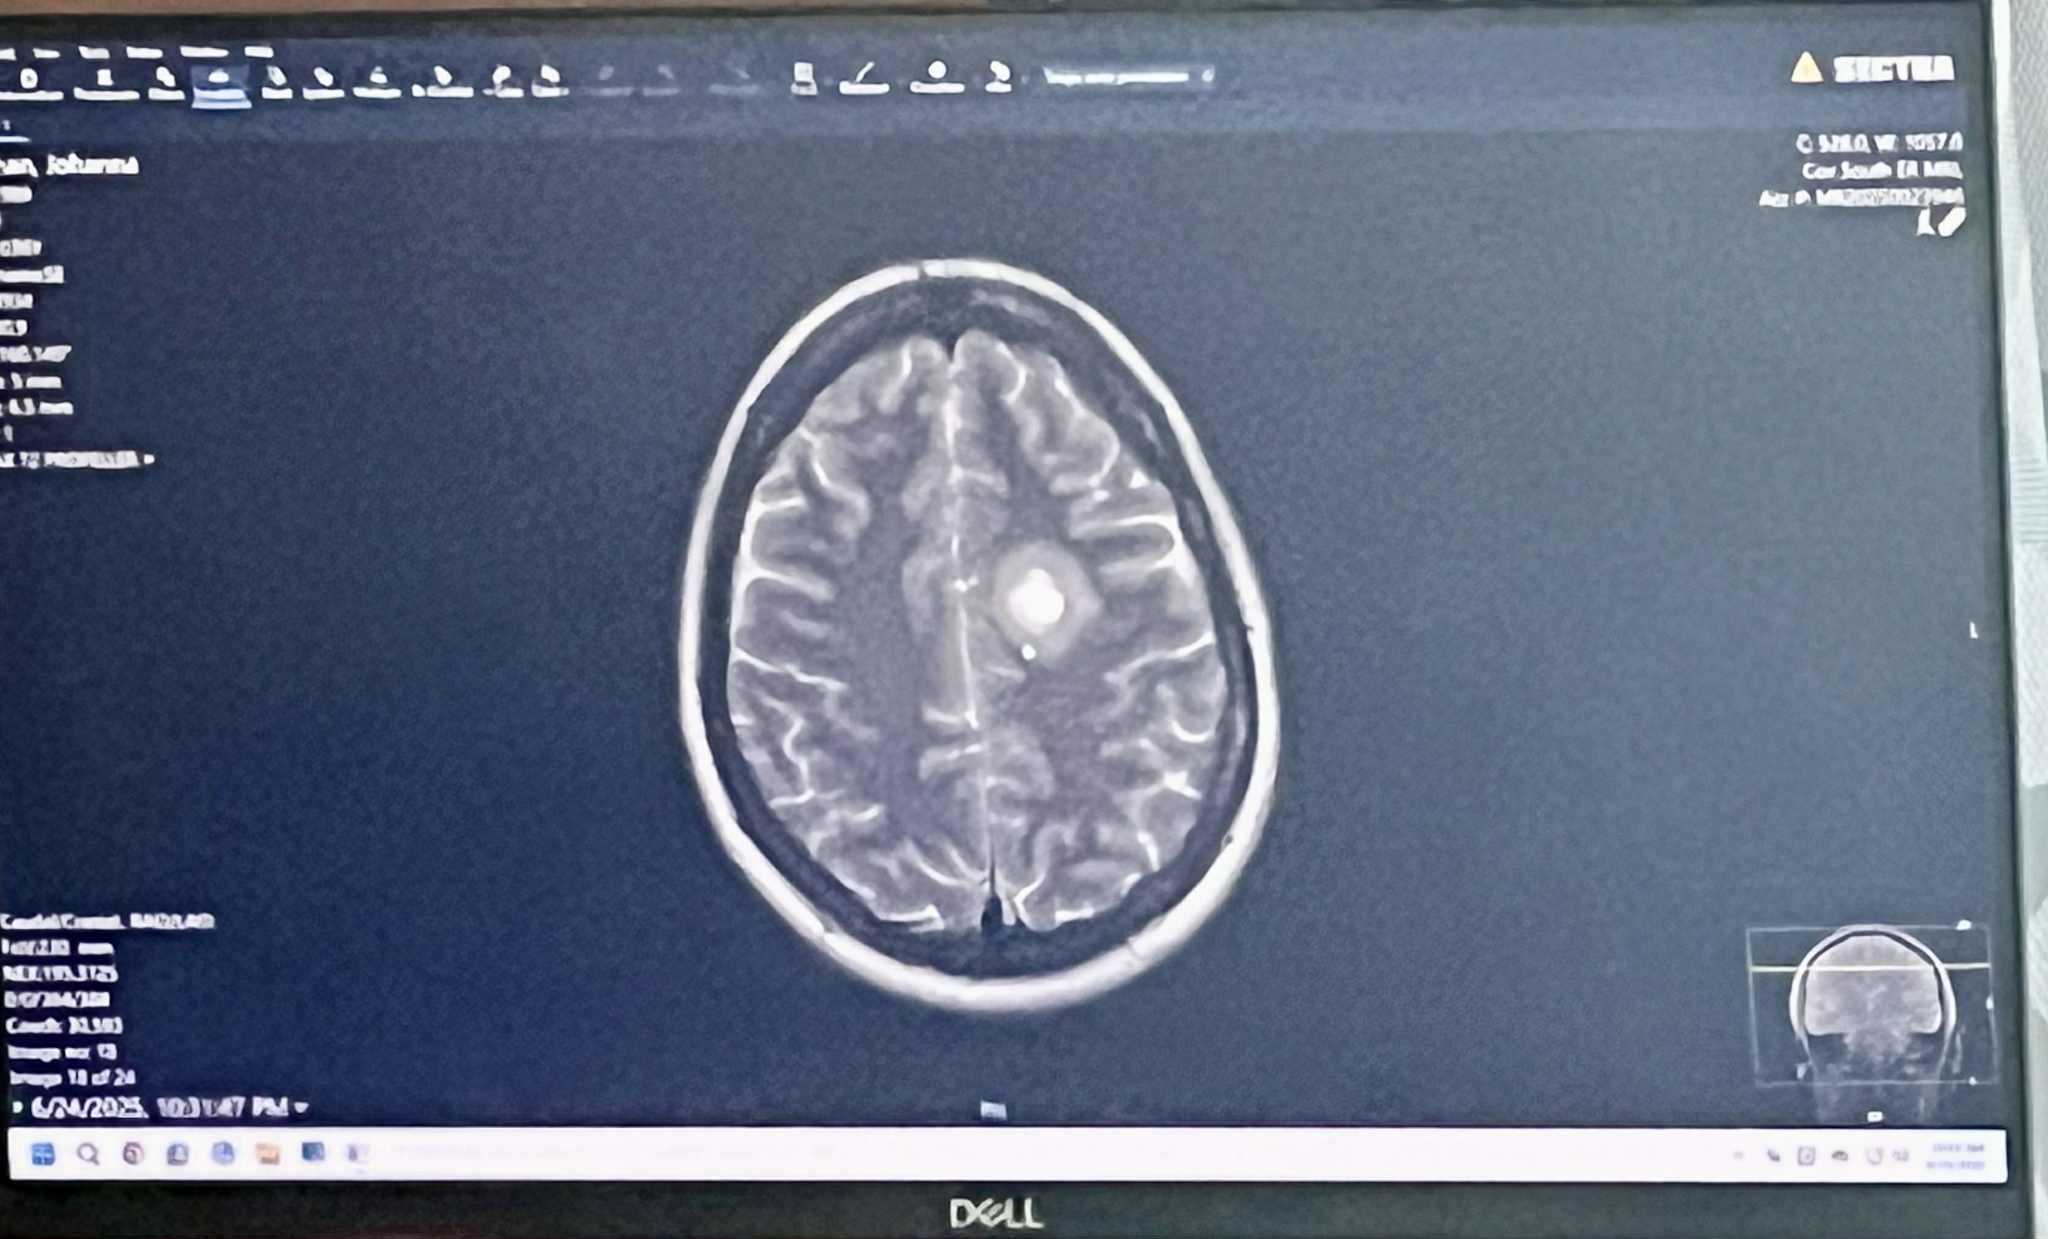

My sister is currently hospitalized with a cancerous brain tumor, a cyst, and significant edema (swelling) in her brain. She’s an inpatient at Springfield CoxHealth, room 845, about 1.5 hours from home, and will remain there through at least Saturday morning while doctors run full-body scans to check for additional tumors and perform a functional MRI to determine if and how her tumor can be safely removed.

In addition to symptoms caused by the tumor, she is now considered at risk for seizures. She’s being treated with steroids to reduce brain swelling, insulin, and continues thyroid care. Her medical team has also placed her on a strict diet requiring 180g of protein daily to support her body during this time.